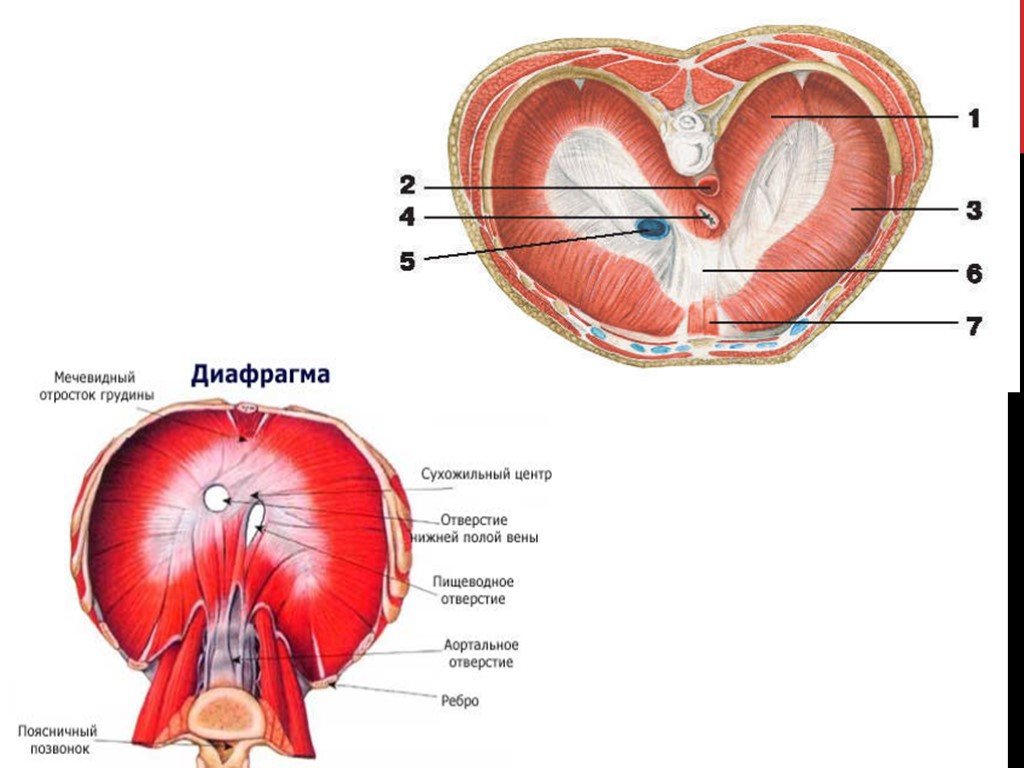

Анатомия диафрагмы и треугольника Бохдалека

Раздел: Визуальный дайджест